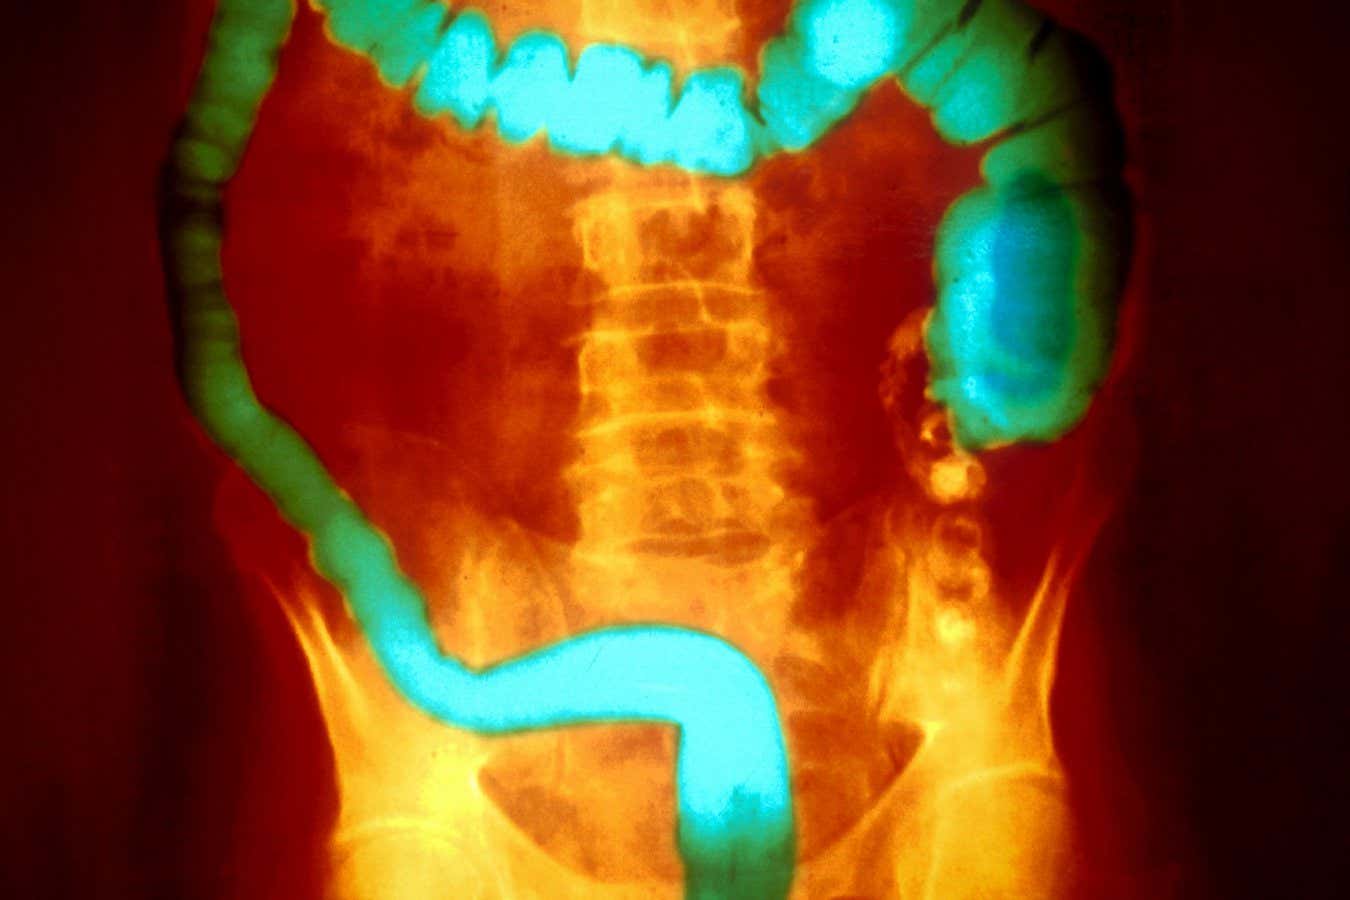

Ülseratif kolit, kolon ve rektumun iç zarının iltihaplanması ile karakterizedir

Ülseratif kolit, iki ana inflamatuar bağırsak hastalığı veya IBD türünden biridir. Kolon ve rektumun astarının iltihaplanması ile karakterizedir. İnsanlarda genellikle alevlenmelerle değişen semptomsuz dönemler vardır. En ciddi vakalar kolonun çıkarılmasını gerektirebilir.